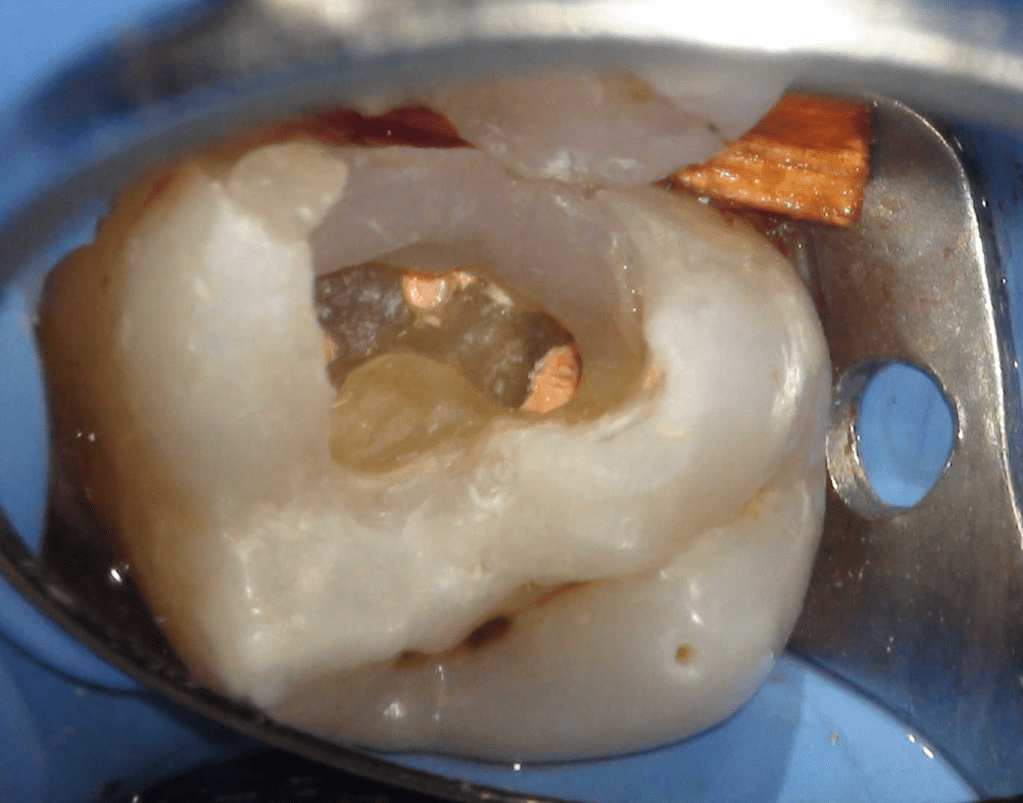

Pulpotomía biodentine + reco preendio